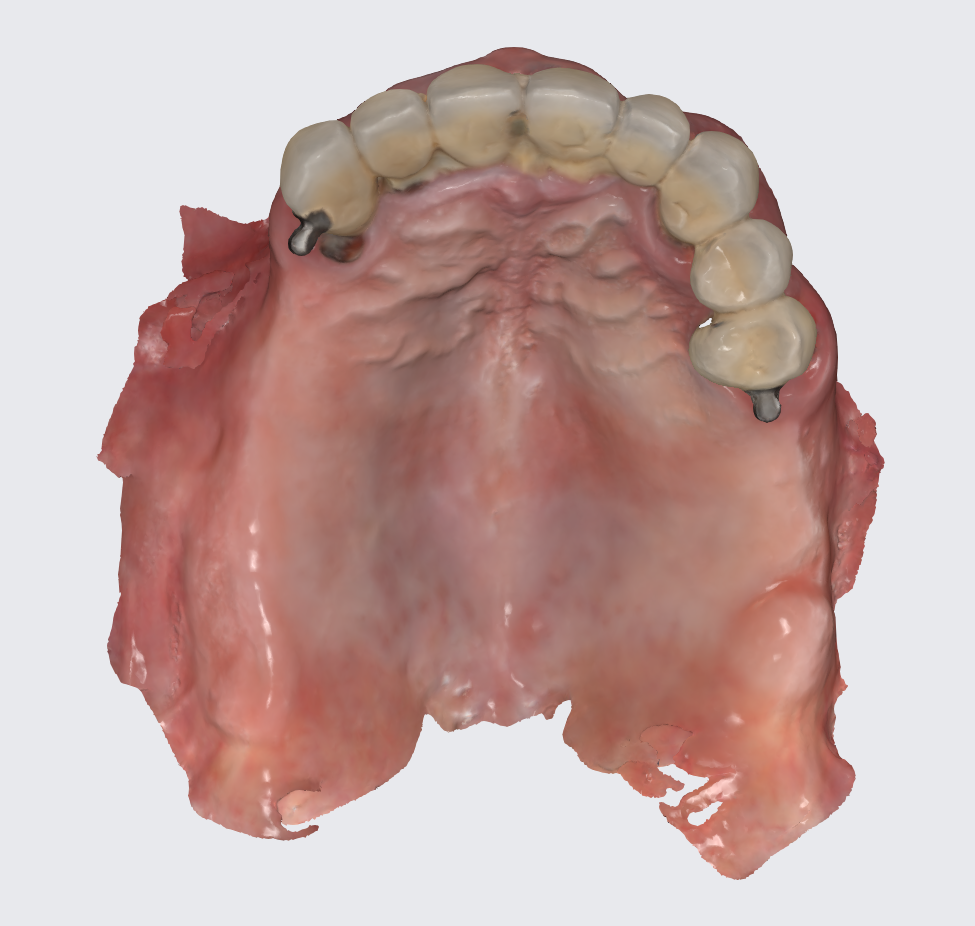

To prepare for the maxillary all on X procedure patient had the upper denture relined with impression material and also multiple dots of radio opaque filling material where temporarily placed on the said denture. Then the 2 dentures where scanned. Also scans of the healed tissues and of the face where recorded.

Using the Aoralscan Elite intraoral scanner (Shining 3D), detailed scans of edentulous ridges and interim prostheses were recorded efficiently and accurately. Edentulous arch scanning proved precise and rapid, significantly simplifying the workflow.

Another view of the post graft healing in the mandibular arch and visibility of the composite marker additions done on the upper denture for alignment purposes between scan image and CBCT datasets.

A new waxup was generated in Exocad and printed as a try in to check occlusion but also esthetics at some degree and have a proprosthetic implant positioning available in the planning step.